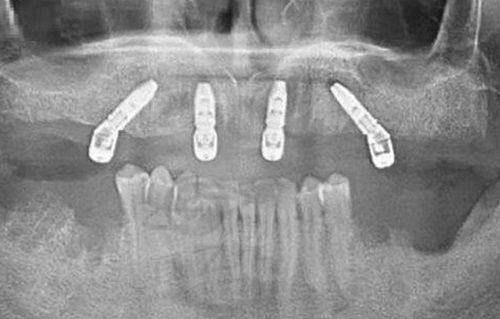

特色技术“一日得”全口种植:兰州海涛口腔医院以“一日得”全口种植技术为特色,这对于半口或全口缺失牙患者来说是一大福音。传统的牙齿种植可能需要多次手术,患者等待时间长,而且在等待过程中生活受到较大影响。而“一日得”种植技术可实现当天种牙、当天佩戴固定义齿、当天正常饮食。患者不用长时间忍受缺牙的不便,大大提高了生活质量。

微创微痛种植技术:同时,医院还采用微创微痛种植技术。这种技术能减少手术创伤,使患者术后修复快。在种植过程中,患者的疼痛感也会大大降低,术后肿胀、出血等情况也相对较少,让患者在轻松的状态下完成牙齿种植。